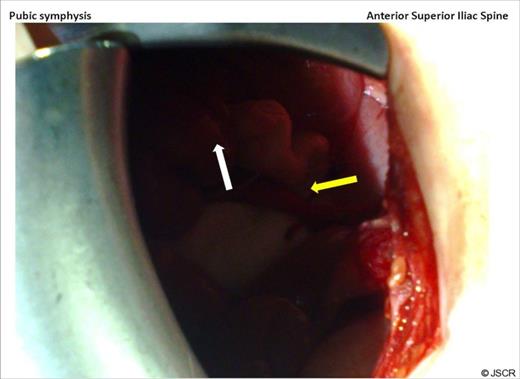

Through a right iliac fossa transverse incision there was no phlegmon. The appendix was found in the inguinal canal with its tip communicating with the skin and exuding faeces. (Figure 3) An appendicectomy was performed. Histopathology revealed a non-inflamed appendix with dilated serosal capillaries, suggestive of trauma and an opening at its tip.

At laparotomy, looking down at the pelvis through a right iliac fossa transverse incision, caecum is seen (white arrow) and the appendix with its tip (yellow arrow) can be seen lying in the inguinal canal.